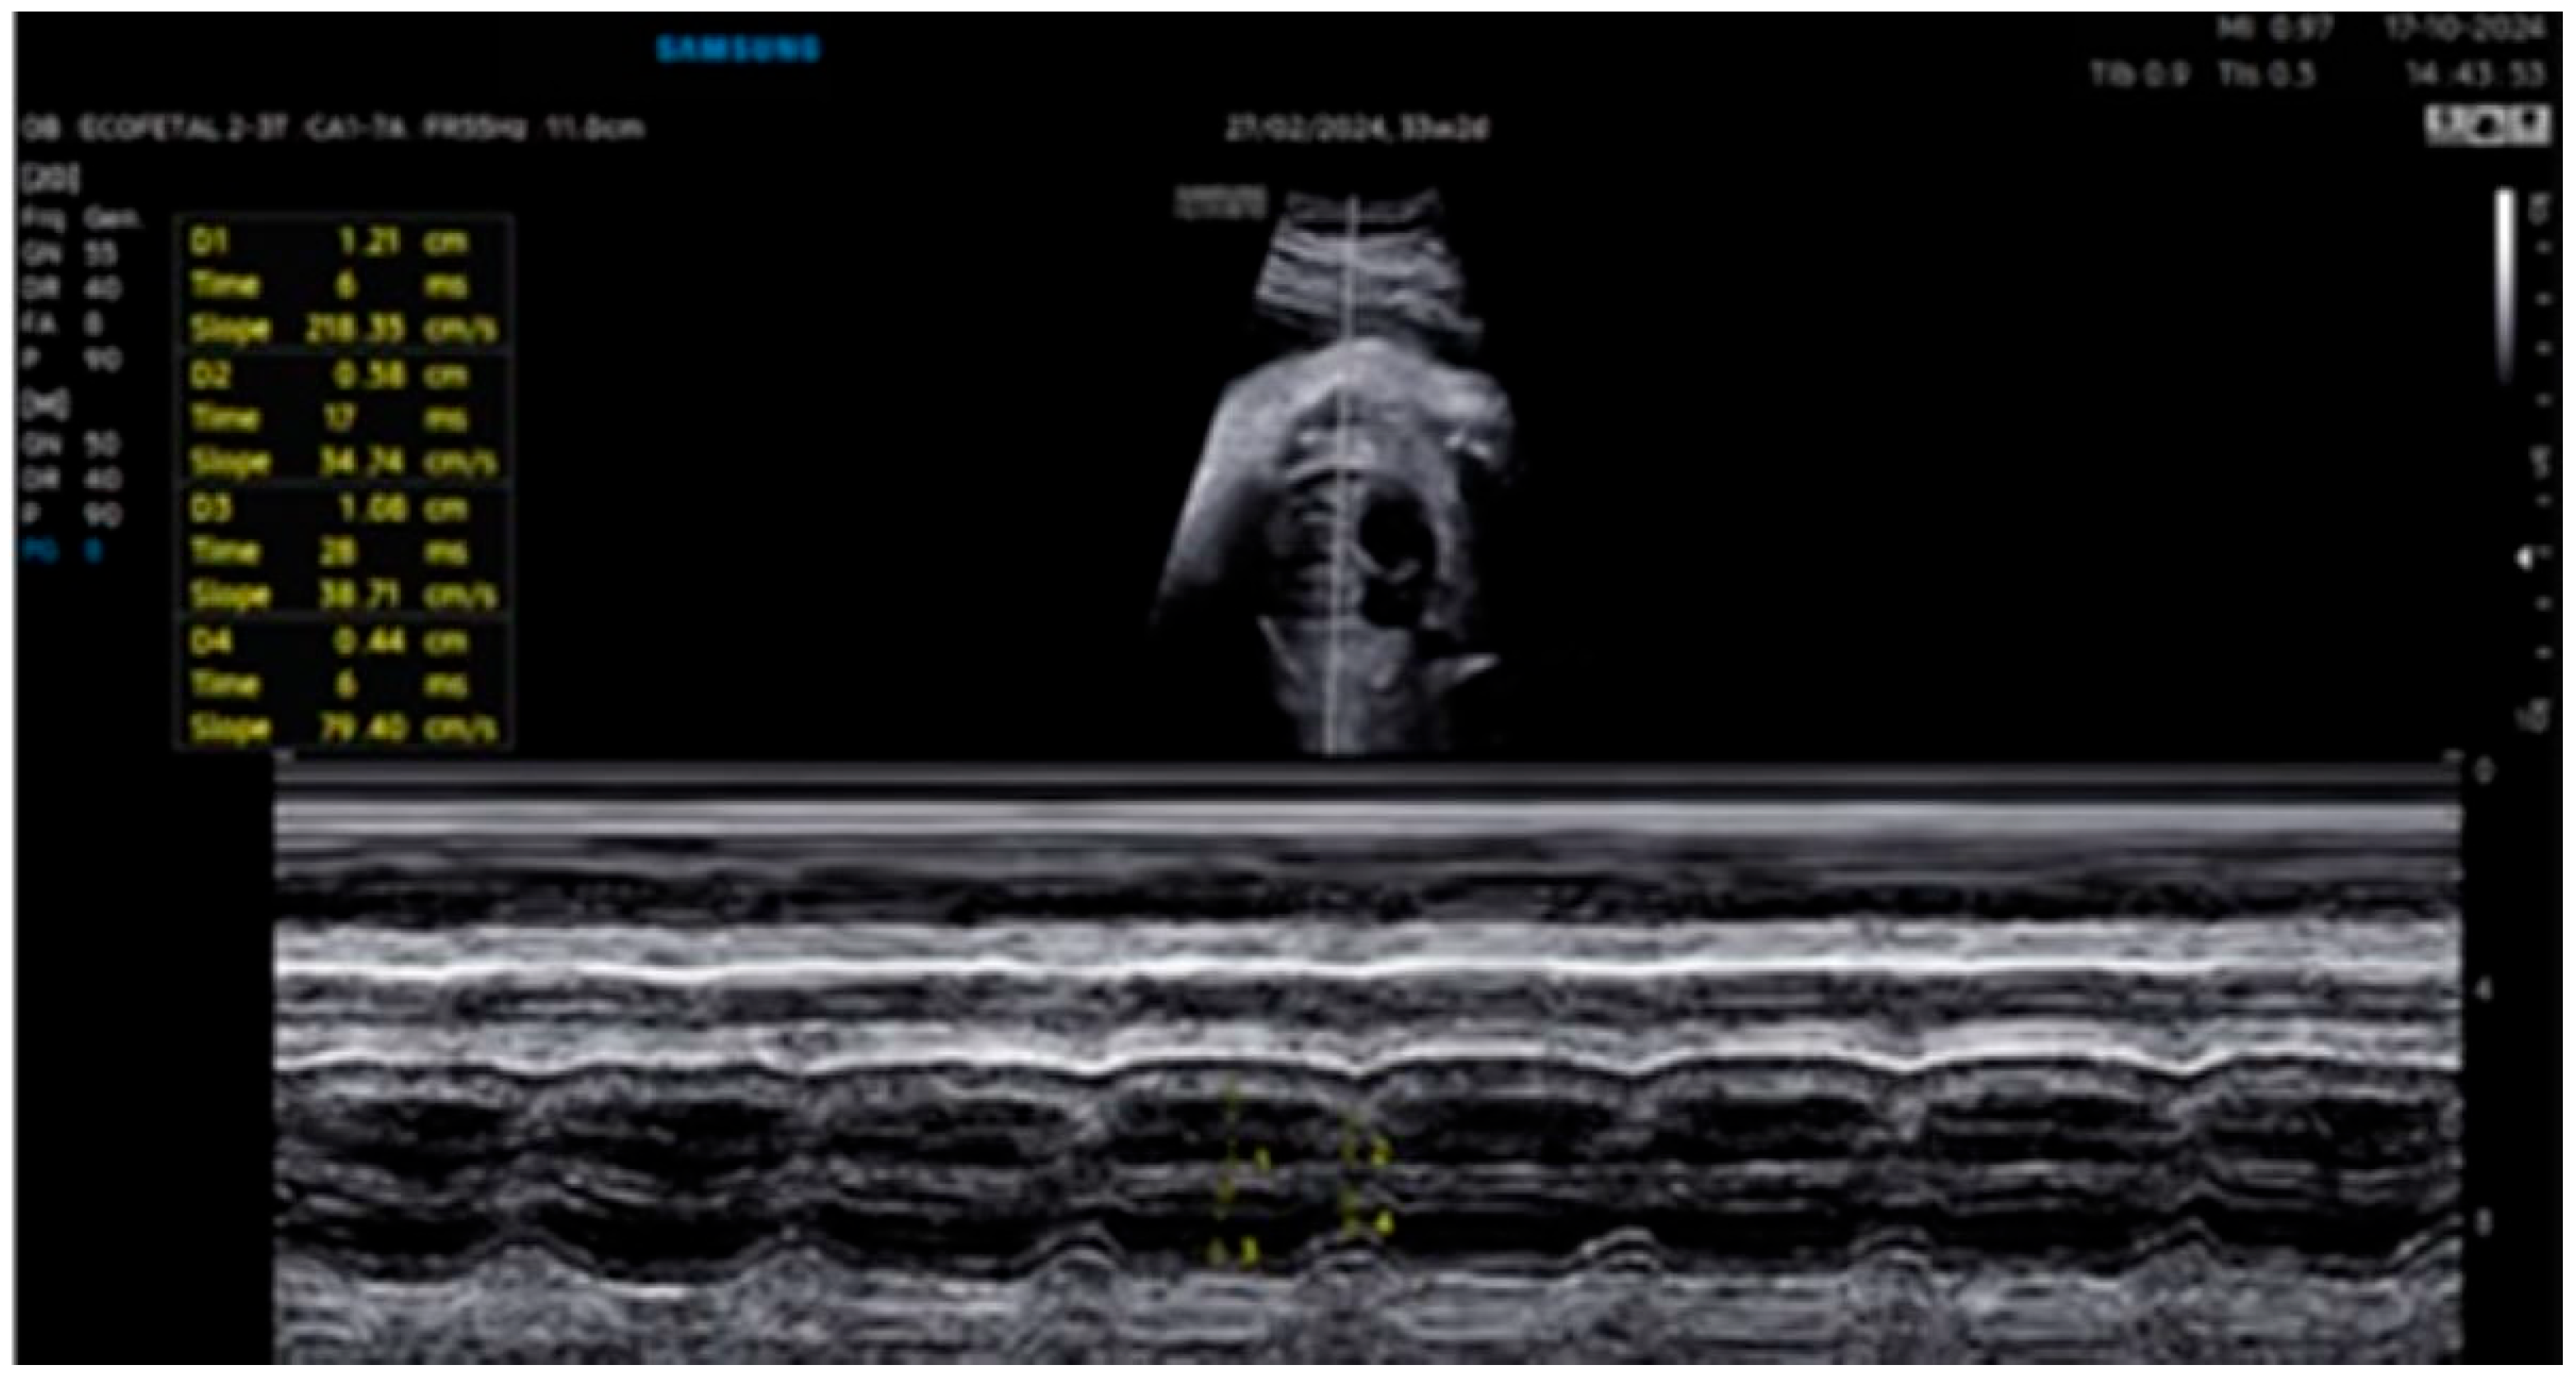

| 31 + 2 | Post-IVIG peak response | 70 | SF: 59% (LV), 52% (RV); marked biventricular improvement | Aortic isthmus 3 mm (Z-score –1.65) |

| 33 + 0 | Second IVIG cycle | 68 | Stable function maintained | Repeated full protocol; no complications |